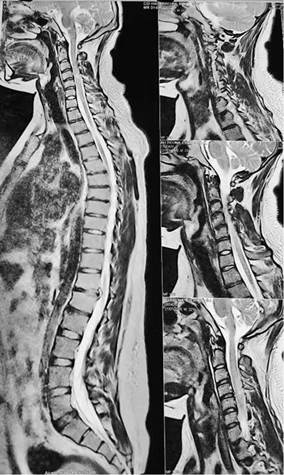

Se trata de un paciente masculino que responde a las iniciales E.A.T. de 24 años de edad, natural y residente de la ciudad de La Paz, sin antecedentes patológicos y familiares de importancia; su cuadro clínico se inicia en marzo de 2022 posterior a sufrir un asalto y agresión con arma blanca, produciéndole herida punzocortante profunda en región cervical derecha de aproximadamente 3 centímetros de longitud; fue evaluado en el servicio de emergencias del Hospital La Paz y posteriormente derivado al Hospital de Clínicas Universitario; se realizaron estudios complementarios como Resonancia Magnética con contraste ponderada en T2 sagital en la que se evidencio una señal hiperintensa en relación a lesión medular aguda a nivel de C4-C5 que se comunica con el canal espinal. Protrusión posterior discal del disco T12 - L1 con desgarro anular central y protrusión que indenta el saco Tecal ventral; el disco presenta disminución de la hiperintensidad y del espacio intervertebral. (Figura 1)

La imagen ponderada en T1 sagital a nivel de C4- C5 muestra señal hipointensa que denota lesión a predominio de la porción posterior de la circunferencia de la medula espinal en corte coronal la imagen ponderada en T2 muestra señal hiperdensa que corresponde a una lesión medular a predominio de hemicordon derecho en C4-C5 (Figura 2 y 3). Se realizo interconsulta a la especialidad de Medicina de Rehabilitación por la especialidad de Neurología; al examen físico presento hemiparesia braquio crural derecha (ipsilateral a la lesión) con un balance muscular de -3/5 en la escala de Daniels además de alteración en la sensibilidad táctil gruesa y propioceptiva; hipoalgesia, hipoestesia térmica e hipoestesia táctil fina en hemicuerpo izquierdo (contralateral a la lesión).